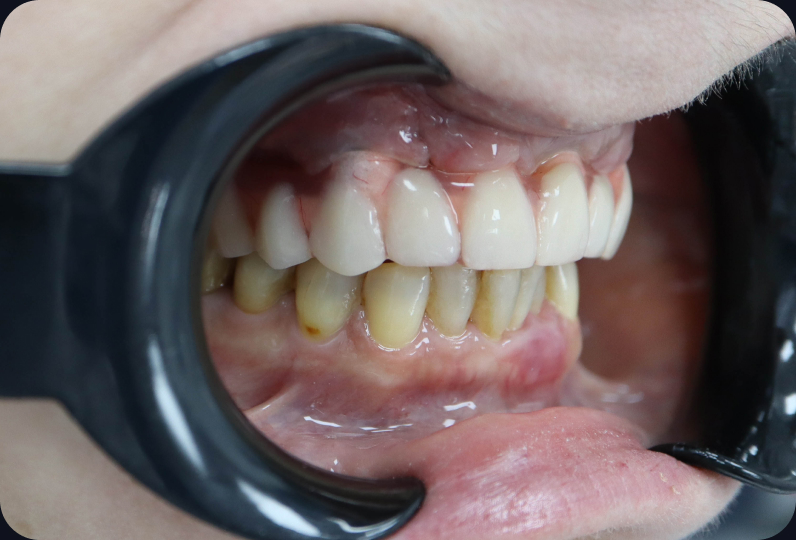

Установлен условно-съемый металлоакриловый протез на 12 зубов

ALT

Вид протеза сбоку

Спустя 7 дней на верхней челюсти зафиксирован металлоакриловый протез из 12 зубов.